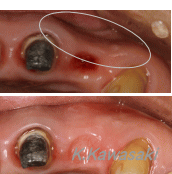

| 前歯の作り直しを希望して来院されました。色・形態・大きさなど審美的ではありません。 |

精密検査の結果、骨の中で歯が割れていることが判明しました。残念ながら抜歯となりました。 |

通常抜歯した部分の歯茎はすぐに痩せてしまいます(○の部分)。外科的に歯茎を増やさなければ美しい歯を入れることはできません。 |

| 外科処置後、ジルコニアのクラウンを装着し審美性を回復しました。 |

どの歯を抜歯したかおわかりでしょうか? |

黄色の○の部分が抜歯した歯です。 |